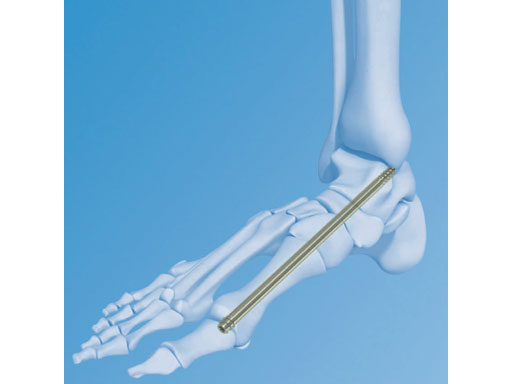

6.5 mm Midfoot Fusion Bolt

The Midfoot Fusion Bolt (MFB) is a solid 6.5 mm intramedullary implant that can be used to stabilize and fuse the medial columnthe metatarsocuneiform, naviculocuneiform, and talonavicular joints. Alternative uses of the MFB may also be for fusing the lateral column, calcaneocuboid, and 4th metatarsocuboid joint. The MFB aims to achieve permanent fusion of these joints in patients suffering from gross instability such as Charcot neuroarthropathy with or without collapse of the midfoot. The midfoot fusion bolt is a headless solid bolt. It enhances stabilization and alignment, restraining shearing and bending forces better than older implants (I-bolt, 6.5 mm cancelleous screw, and 6.5 mm and 7.3 mm cannulated screws). The MFB is recommended for stabilization of the medial column or fixation of the lateral column. The bones and joints are aligned, measured and drilled with cannulated instruments. The guide wire is removed. The bolt is inserted through the track created by the 5.0 mm drill. Controlled compression may be applied by the T-handle during insertion. After insertion, the bolt head is completely countersunk preventing soft tissue or joint irritation. A blunt tip prevents any damage to soft tissues if the MFB is overinserted.

The MFB is available in lengths of 50160 mm in titanium and stainless steel.